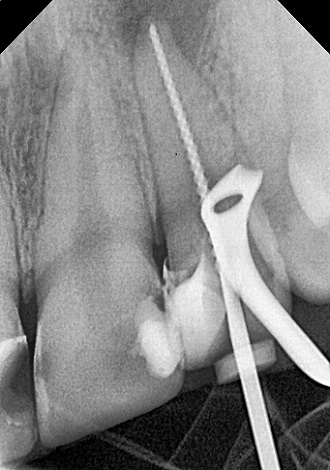

5. визначити глибину каналів зубного

кореня;

6. механічна розробка каналів;

7. хімічна обробка каналів;

8. герметична обтурація.

Пломбування кореневих каналів.

Якісно запломбовані кореневі канали є основою

довговічності. Тому очищення і пломбування кореневих каналів в «Домі Стоматології»

приділяється особлива увага! Після пломбування кореневих каналів проводиться

контроль якості пломбування за допомогою знімка.